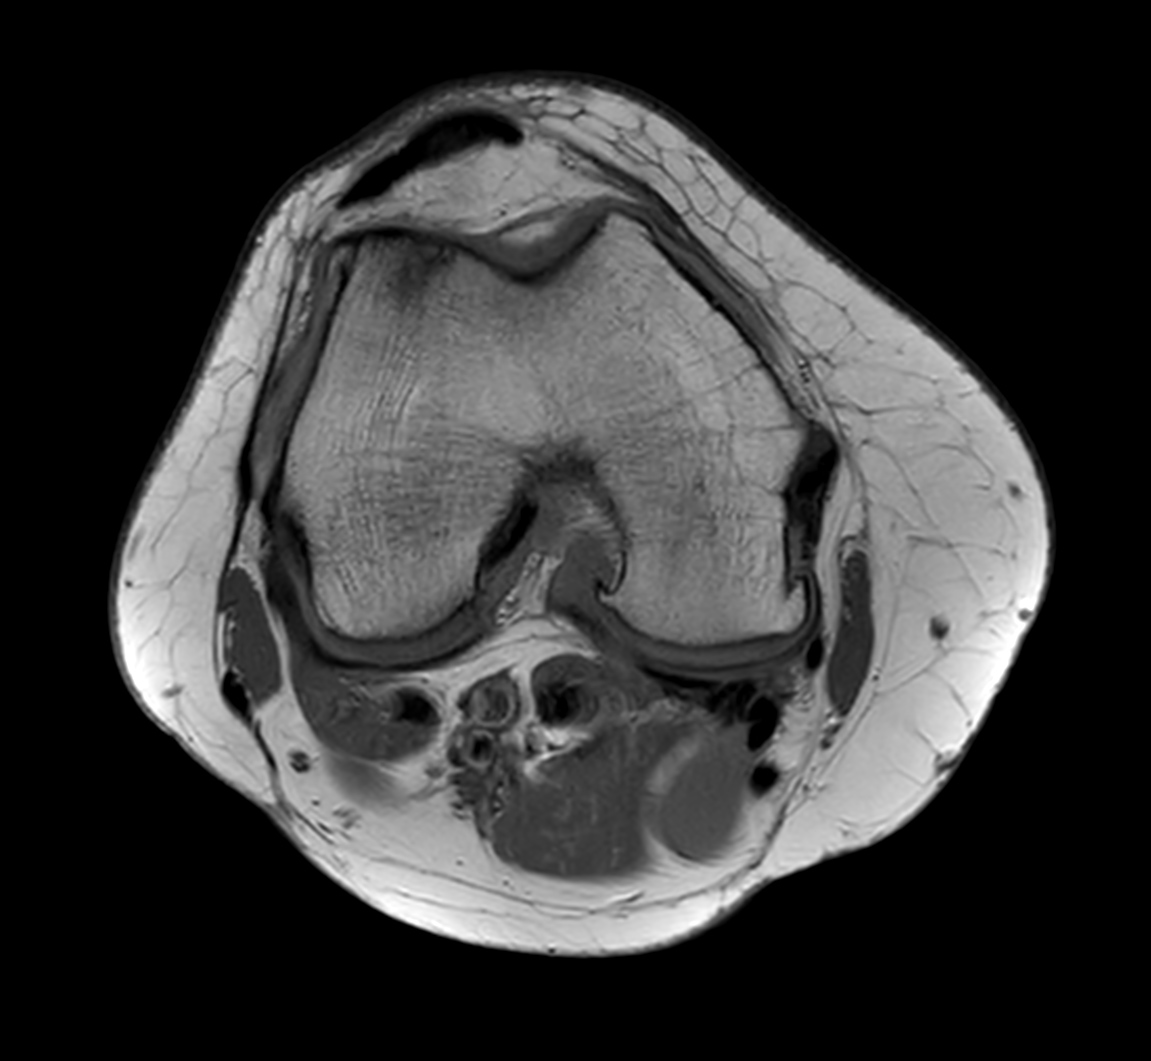

Axial T2w calc (source)